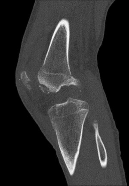

Question 3:

A 22-year-old soccer player sustains a twisting injury to his knee during a match. Radiographs reveal a small elliptical bone fragment adjacent to the lateral tibial plateau (Segond fracture). Based on this radiographic finding, which physical exam maneuver is most likely to be positive in this patient?

Correct Answer: Positive pivot shift test

A Segond fracture is an avulsion fracture of the anterolateral ligament (ALL) and lateral capsule from the lateral tibial plateau. It is highly pathognomonic (up to 75-100% predictive value) for an anterior cruciate ligament (ACL) tear. The pivot shift test is the most specific physical examination finding for assessing rotational laxity associated with an ACL-deficient knee.